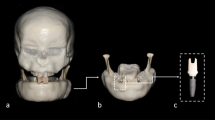

The water phantom was used to calculate SNR, U, and distortion. The central or nearly central slices of the phantom was used in analyzing the region of interest (ROI). Five featureless circular ROIs were chosen in which the diameter of each ROI accounted for 20% of the diameter of the phantom (Fig. 1).

Diameter was determined as the circumference of the ROI around its outline (Fig. 1).

As shown in Fig. 2, image deformity was defined in terms of roundness, which was measured in accordance with the out-of-roundness standard ANSI-B89.3.1 [14], as follows: